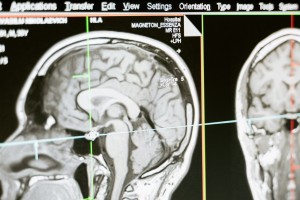

Multiple Skleroz (MS), merkezi sinir sisteminin (beyin ve omurilik) iltihaplanması ve hasar görmesiyle karakterize edilen kronik bir nörolojik hastalıktır. Bu kategori, Multiple Skleroz'un farklı yönlerini ve etkilerini ele alan içerikleri barındırmaktadır.